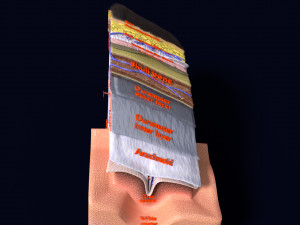

A blend model of brain along with its covering layers (meninges), skull bone and scalp labelled in detail and anatomically precise. The parts depicted are white, gray, pia, arachnoid, dura, bone, skin, fat, aponeurosis, periosteum, falx cerebri and more.

The material is high resolution image textures and normal maps based on non overlapping UVs. The texture and normal maps are packed with the blend file itself.